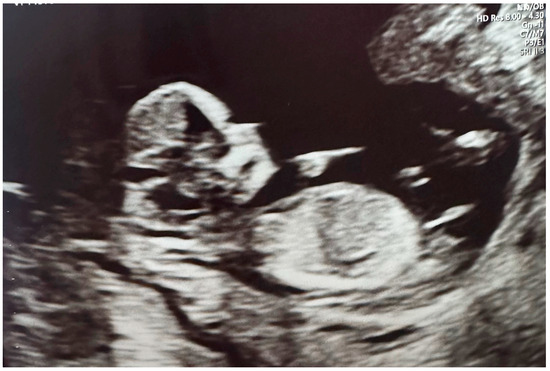

- Planned Natural Conception

- First Trimester PBM Treatments